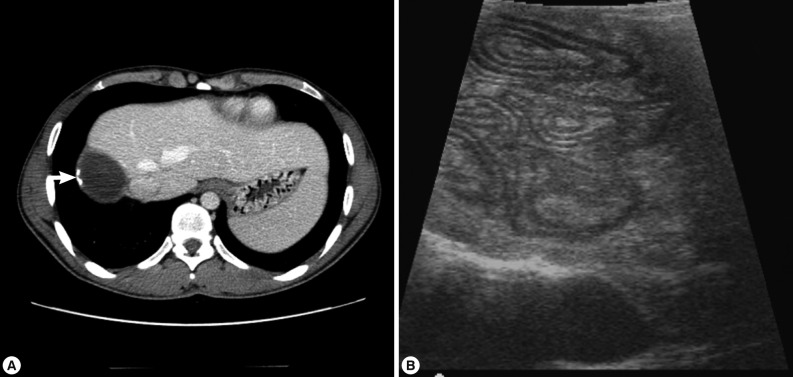

An Imported Case of Cystic Echinococcosis in the Liver

The Korean Journal of Parasitology 2012;50(4):357-360.